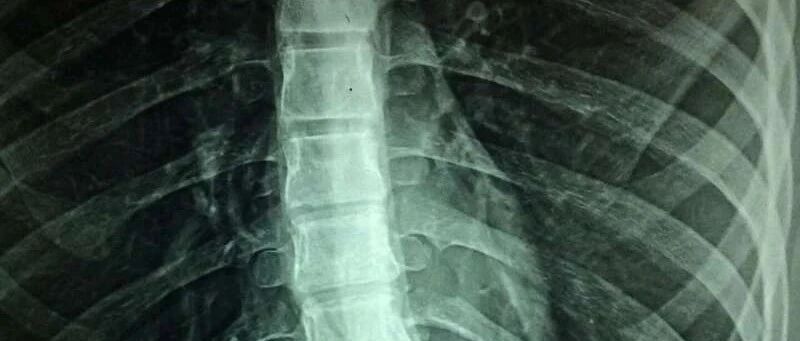

溃疡性结肠炎:溃疡性结肠炎是一种病因尚不十分清楚的结肠和直肠慢性非特异性炎症性疾病,病变局限于大肠黏膜及黏膜下层。病变多位于乙状结肠和直肠,也可延伸至降结肠,甚至整个结肠。病程漫长,常反复发作。本病见于任何年龄,但20~30岁最多见。症状以腹泻为主,排出含有血、脓和黏液的粪便,常伴有阵发性结肠痉挛性疼痛,并里急后重,排便后可获缓解。镜检可看到黏膜表面充血、水肿、以及周围隆起的肉芽组织;通过肠镜可确诊。目前首选治疗药物为美沙拉嗪。我科在治疗溃疡性结肠炎有丰富经验,采用口服美沙拉嗪+药物保留灌肠取得了比较满意的疗效。

克罗恩病:本病病因不明,可能与感染、体液免疫和细胞免疫有一定关系。克罗恩病为贯穿肠壁各层的增殖性病变,可侵犯肠系膜和局部淋巴结,病变局限于小肠(主要为末端回肠)和结肠,二者可同时累及,常为回肠和右半结肠病变。多见于青壮年。

黏膜面典型病变有:1.溃疡;2.卵石样结节;3.无干酪样变肉芽肿;4.瘘管及脓肿形成。常见临床表现为腹痛、腹泻、脓血便、腹块、瘘管形成。常伴有发热及消瘦。肠镜是检查克罗恩病最敏感的检查手段。目前常见的治疗手段为免疫抑制剂,但是由于肛周常伴感染性瘘管及脓肿形成,需及时行切开排脓引流术控制感染后方可行免疫抑制剂治疗。炎症性肠病对于病情严重有严重并发症或者病理发现癌变者应及时行外科手术治疗。